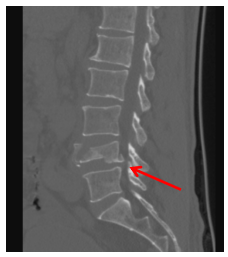

惊险一摔,脊柱“矮”了一半——手术迫在眉睫。患者因不慎从高处跌落,腰部着地,当即感到腰部剧烈疼痛,无法站立和活动。送至阿坝州人民医院后,经CT及三维重建检查,被明确诊断为:腰4椎体压缩性骨折,椎体前缘压缩高度达50%(约1/2),折块向前后移位,局部骨性椎管变窄,椎旁软组织肿胀。

(术前CT)